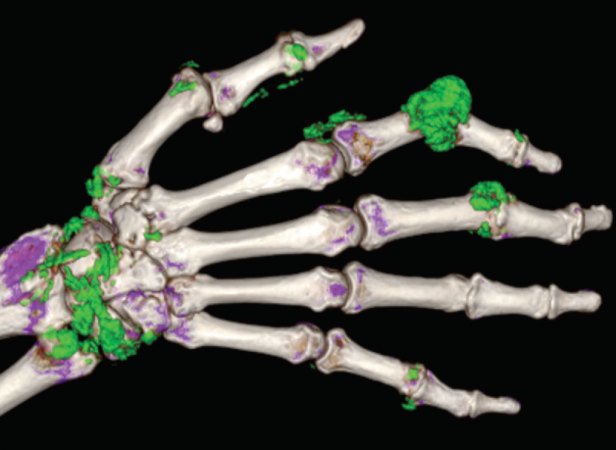

Thanks to a technique called dual-energy CT, doctors were able to pinpoint the problem. Dual-energy CT, introduced in 2006, uses two beams of X-rays at different energies, instead of just one beam. Taking images this way allows the scanners to work out exactly what materials are within. Different materials absorb X-rays in different amounts, but in order to zero in on a specific type of material, you want to know how that absorption changes as the X-rays’ energy changes.

For example, dual-energy CT can distinguish between different types of crystals that can form in the joints, causing arthritis. Urate crystals indicate gout, and crystals containing calcium point to pseudogout. For McCollough’s father-in-law, the scan quickly uncovered the cause of his pain: pseudogout. In this way, CT scans can reveal the human body at its most basic level, the materials that make it up.